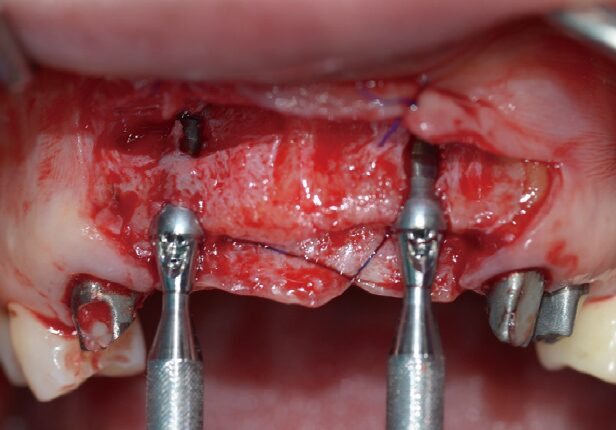

AXA positioning